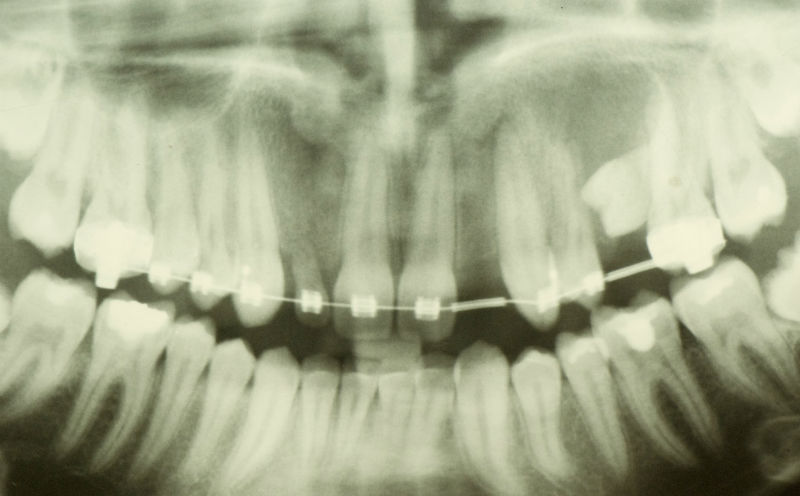

Лечение с брекети за осигуряване на място за зъбни импланти.